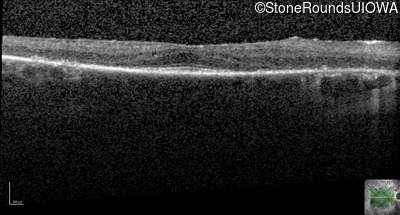

Optical Coherence Tomography - Left - 20/20 -2

Exemplar / OCT Stack